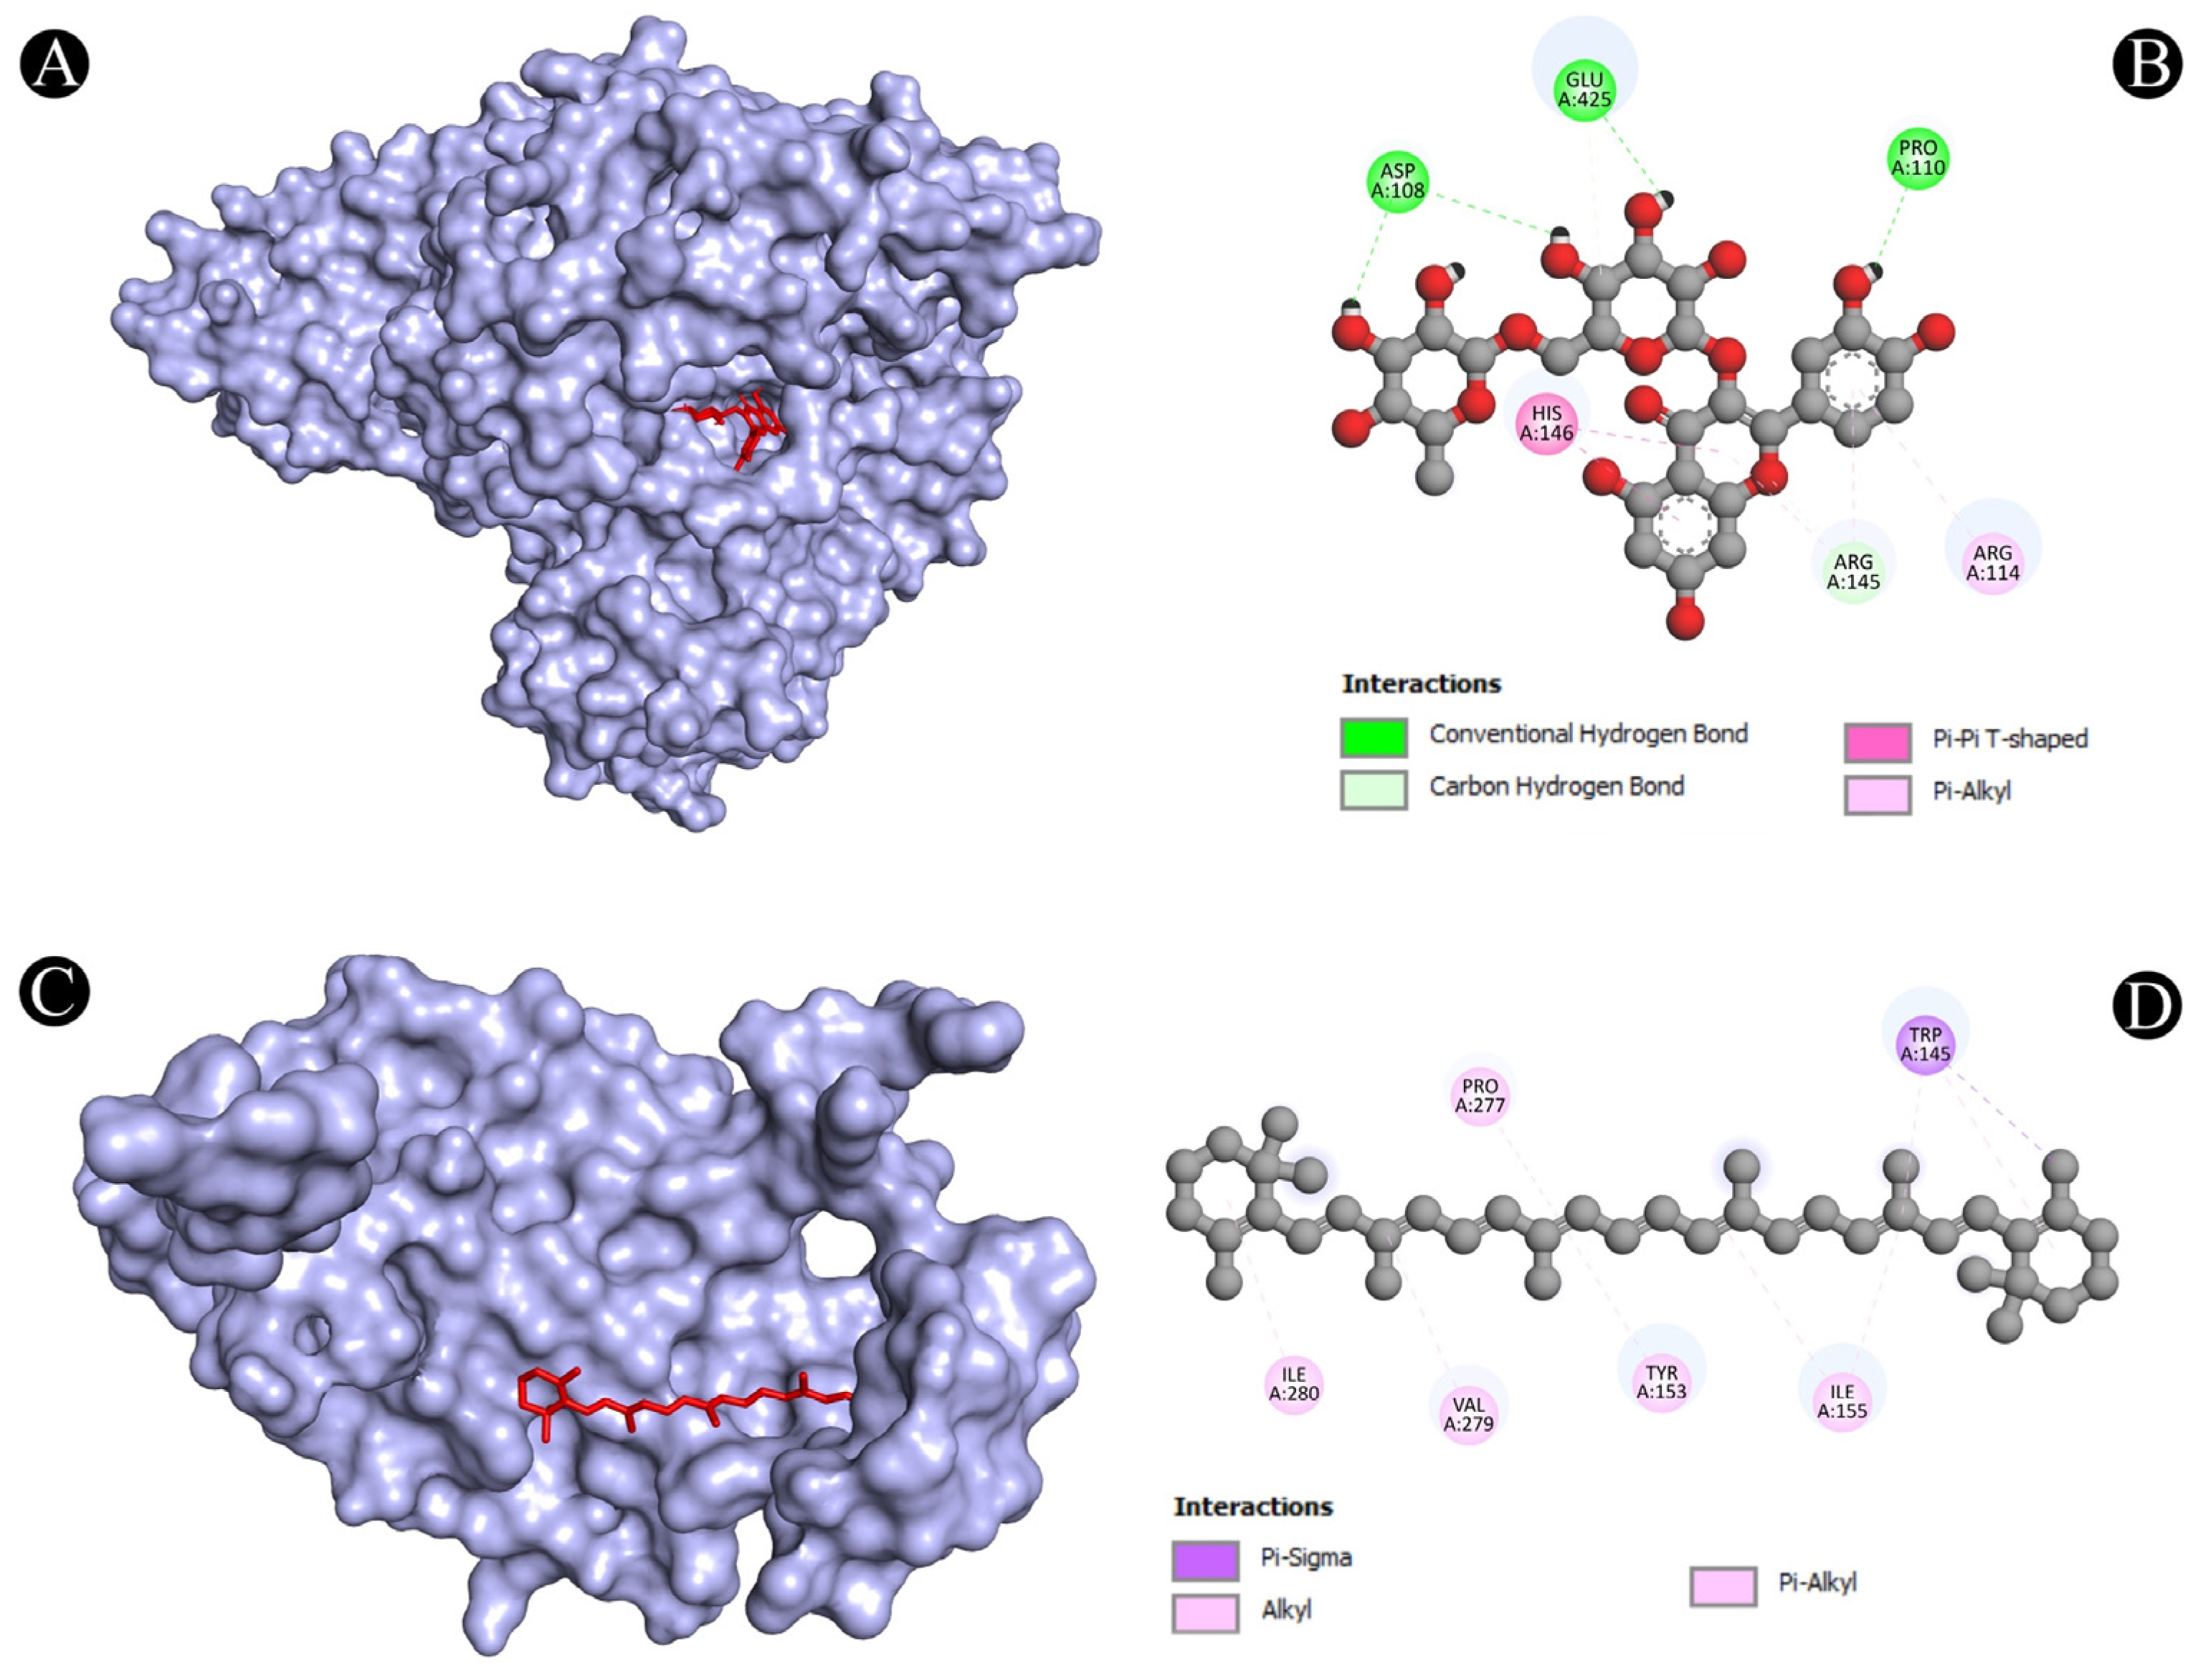

3.4. Molecular Docking Analysis